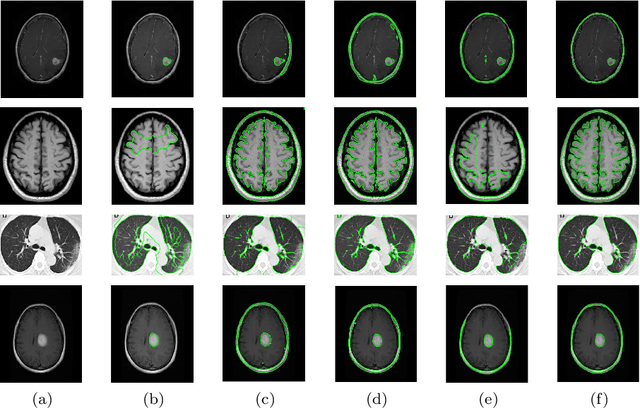

In order to improve the robustness of traditional image segmentation models to noise, this paper models the illumination term in intensity inhomogeneity images. Additionally, to enhance the model's robustness to noisy images, we incorporate the binary level set model into the proposed model. Compared to the traditional level set, the binary level set eliminates the need for continuous reinitialization. Moreover, by introducing the variational operator GL, our model demonstrates better capability in segmenting noisy images. Finally, we employ the three-step splitting operator method for solving, and the effectiveness of the proposed model is demonstrated on various images.